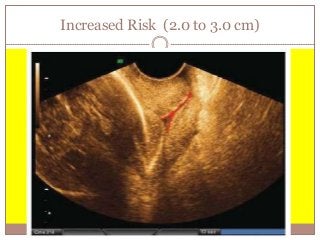

Increased Risk (2.0 to 3.0 cm)

 Most of these women do NOT deliver preterm.

 FFN testing indicated.

 If FFN positive  See High Risk Slide.

 If FFN negative  See Low Risk Slide.